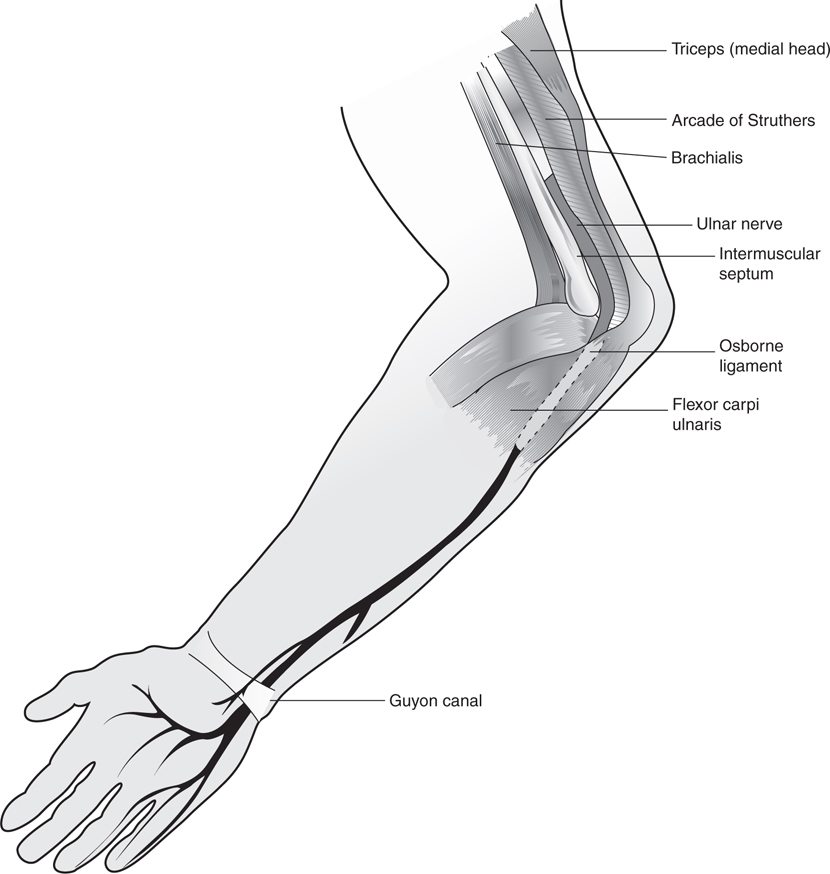

Foot pain due to a nerve entrapmentNerve compression syndrome: what is nerve compression syndrome? Ulnar nerve entrapment: what is it, symptoms, causes, treatment, andPosterior interosseous nerve syndrome/palsy.

Cubital tunnel syndromeNerve compression syndromes Ulnar nerve syndrome tunnel cubital entrapment compression enlarge clickNerve extremity compressions orthopaedicprinciples compression.

Compression nerveSyndrome palsy radial nerve tunnel posterior interosseous compression sites entrapment diagnosis Compression ulnar nerve sites syndromes figure potentialNerve compression syndrome.